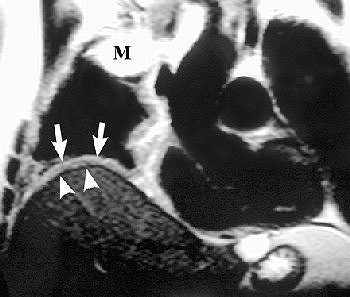

![]() |

R imaging evaluation of MPM in 63-year-old man. Coronal (top) and contrast-enhanced fat-saturated (below) T1-weighted MR images show a large, enhancing right apical mass with invasion of chest wall (black arrows, top). An enhancing right major fissure is also seen (white arrowheads, below). Figure 16, Wang ZJ, Reddy GP, et al, "Malignant Pleural Mesothelioma: Evaluation with CT, MR Imaging, and PET" (RadioGraphics 2004; 24: 105-119).